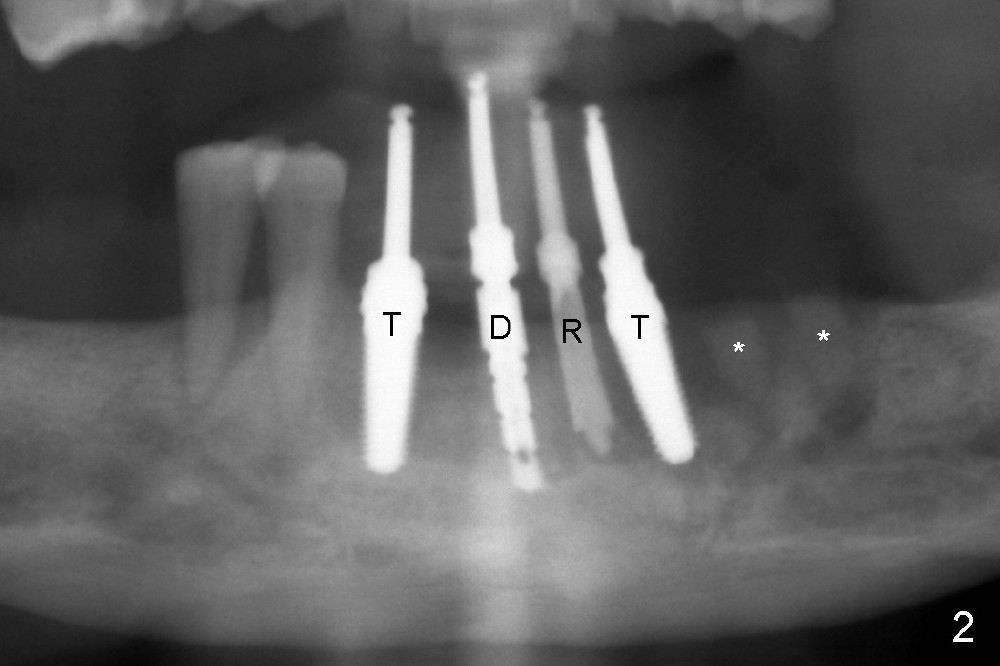

Treatment plan of the 1st surgery consists of extraction of #20 and 21/immediate implants (Fig.1 x), and placement of 4 implants between #22 and 27. Osteotomy at the extraction sites without incision (close surgery) turns out to be difficult; it appears to encroach the inferior alveolar nerve and mental loop. The sockets are subsequently bone grafted (Fig.2 *: mixture of autogenous bone and allograft). Incision is the made in the incisor edentulous region for placement of 3.5x17 mm implants (Fig.3 I).